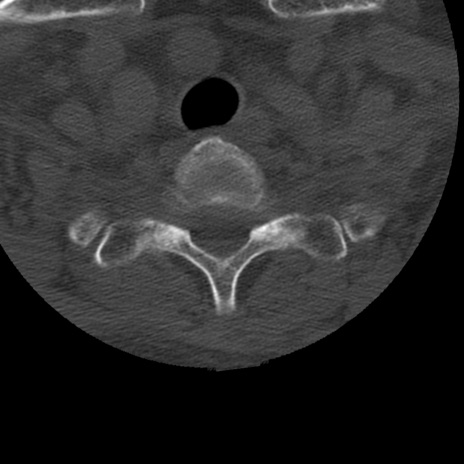

症例50 頚椎CT(横断像)

異常所見と診断は?

頚椎CT